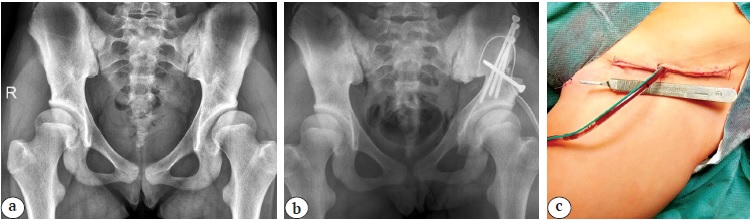

Медиальный трансаддукторный доступ и доступ «бикини». Положение пациента на операционном столе — лежа на спине. На нижней конечности в положении сгибания и разведения на стороне вмешательства выполняется поперечный разрез кожи и подкожно-жировой клетчатки в проекции сухожилия m. adductor longus длиной до 4 см. Тупо в межмышечном промежутке формируется канал до седалищной кости. После поднадкостничного выделения долотом выполняется ее периацетабулярная остеотомия. Следующим этапом производится разрез кожи и подкожно-жировой клетчатки на 1 см ниже крыла подвздошной кости вдоль паховой складки длиной до 15 см. После рассечения фасции визуализируется, выделяется на протяжении и смещается n. сutaneous femoris lateralis. В промежутке между m. tensor facia lata и m. sartorius выделяется крыло подвздошной кости с последующим рассечением его хрящевого апофиза, поднадкостичным выделением тела подвздошной кости и проведением проволочной пилы в седалищную вырезку. Дальнейшие манипуляции не имели отличий от аналогичных, выполняемых из переднебокового доступа (рис. 2).

Рис. 2. Выполнение тройной остеотомии таза из двух хирургических доступов: a — рентгенограмма пациента 16 лет с дисплазией тазобедренных суставов I степени по Crowe до операции; b — рентгенограмма после восстановления корректных соотношений между тазовым и бедренным компонентами тазобедренного сустава методом реориентирующей тройной остеотомии таза слева; c — вид хирургического доступа после ушивания